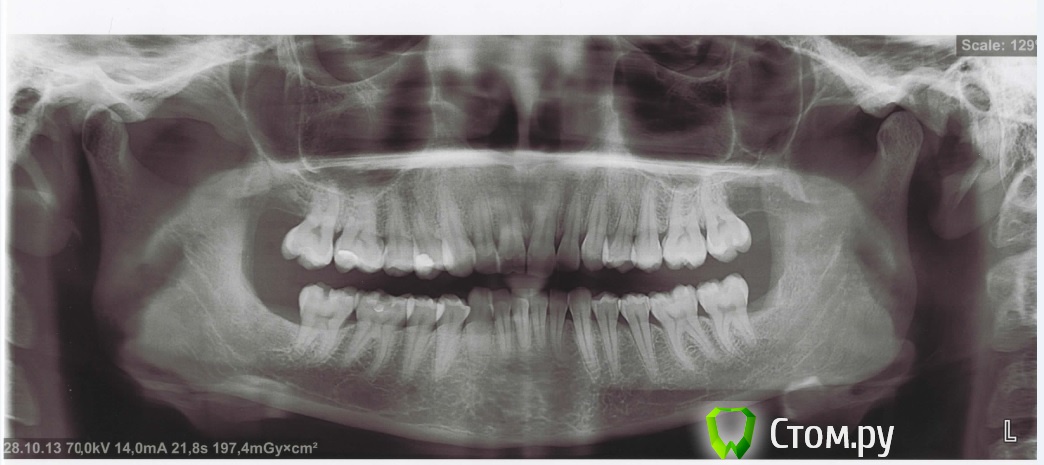

Tirend Опубликовано 25 ноября, 2013 Поделиться Опубликовано 25 ноября, 2013 Добрый день!Собираюсь ставить брекеты. Ходила на консультации к 5 разным ортодонтам. В двух местах предложили просто сразу ставить брекеты, дополнительно зубы удалять не надо (у меня уже удалены все 4 зуба мудрости), нужна будет только сепарация . Ещё в двух местах предложили поставить брекеты ( сначала на верхнюю челюсть, потом через неcколько меcяцев на нижнюю), пока без удаления, через год примерно смотреть ситуацию и тогда решать вопрос об удалении четвёрок, также возможно потребуется установка ортоимплантов в случае удаления. В последнем месте врач пощупала челюсть при смыкании, сказала, что обязательно нужна сплинт-терапия, т.к. нижняя челюсть "ходит". Что у меня смещение центра, об этом говорили все врачи, но сплинт предложили только в одной клинике. Ношение сплинта в течении 3 месяцев круглосуточно, потом обязательное удаление зубов перед установкой брекетов, сколько зубов под удаление - решаться будет только после сплинтов. При жевании щелчков вроде бы нет, болей тоже не замечала. Теперь думаю, нужно ли мне это - ведь это лишние денежные траты и время, хотелось бы уже поскорее начать основное лечение. Также все врачи замечали сужение обеих челюстей, дистальный прикус, экстремальный наклон зубов. Стоит ли пройти сплинт-терапию и сразу удалить зубы перед фиксацией брекетов или лучше начать лечение без удаления и решать этот вопрос в процессе? Ссылка на комментарий